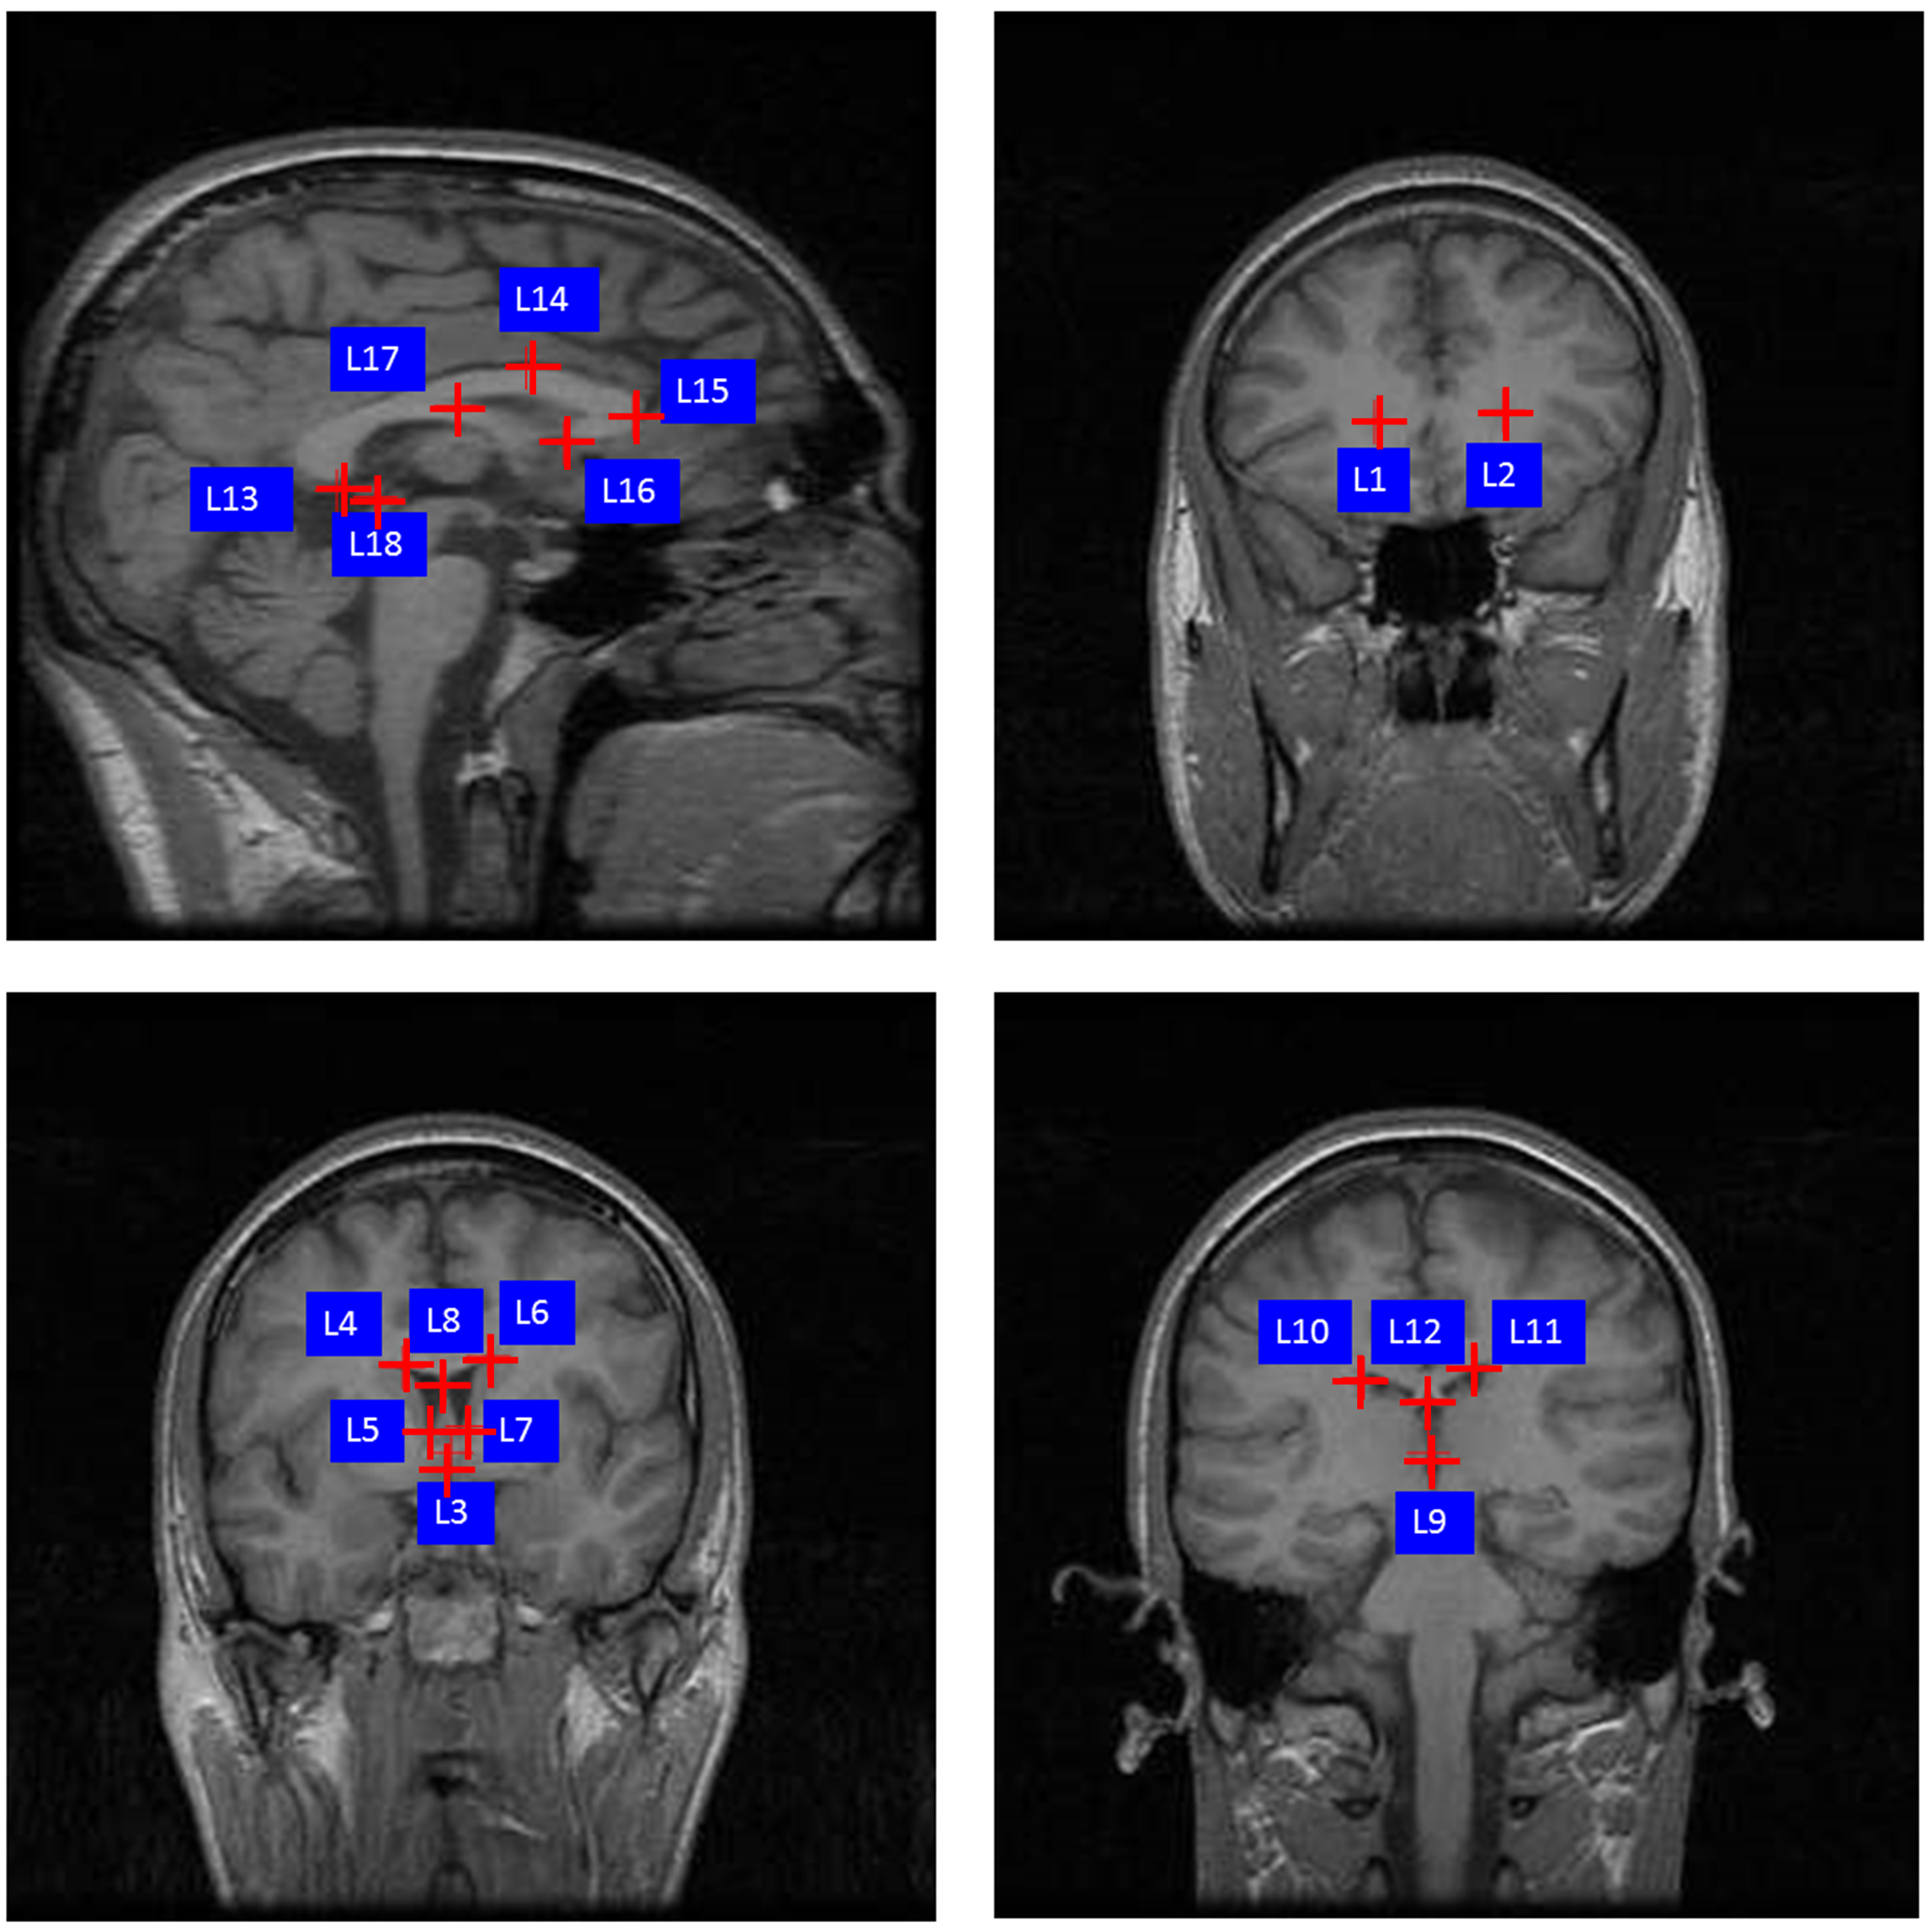

Refer to caption

Figure 4: This sketch illustrates the 18 landmarks selected in the brain dataset. L1: right lateral ventricle posterior, L2: left lateral ventricle posterior, L3: anterior commissure corresponds to the midpoint of decussation of the anterior commissure on the coronal AC plane, L4: right lateral ventricle superior, L5: right lateral ventricle inferior, L6: left lateral ventricle superior, L7: left lateral ventricle inferior, L8: middle of lateral ventricle, L9: posterior commissure corresponds to the midpoint of decussation, L10: right lateral ventricle superior, L11: left lateral ventricle superior, L12: middle of lateral ventricle, L13: corpus callosum inferior, L14: corpus callosum superior, L15: corpus callosum anterior, L16: corpus callosum posterior tip of genu corresponds to the location of the most posterior point of corpus callosum posterior tip of genu on the midsagittal planes, L17: corpus callosum fornix junction, L18: pineal body.